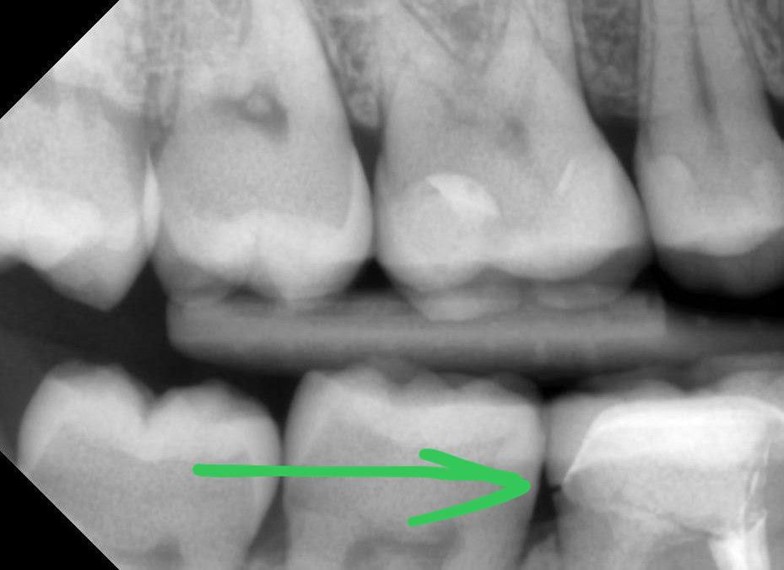

А вот такие снимки нам могут прислать пациенты, с опасением, что выпал имплантат. В действительности, это повреждение ремонтопригодной супраструктуры имплантата. Сам он на месте.